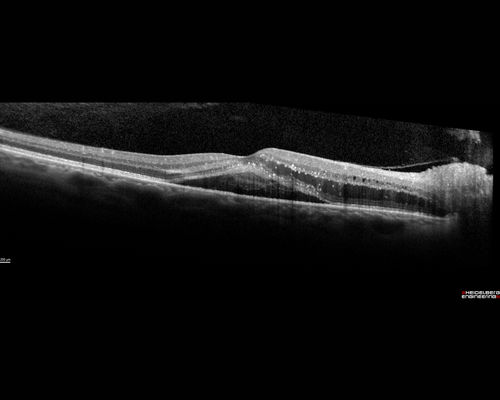

Neuroretinitis - Negative cat scratch serology twice - Possible Behcets

65 year old man with no direct cat exposure and vision loss from neuroretinitis.  His work up was positive for HLA B51.  He had negative cat scratch titers twice.  Vision dropped from 20/60 - 20/200 and then improved to 20/40 over 2 months